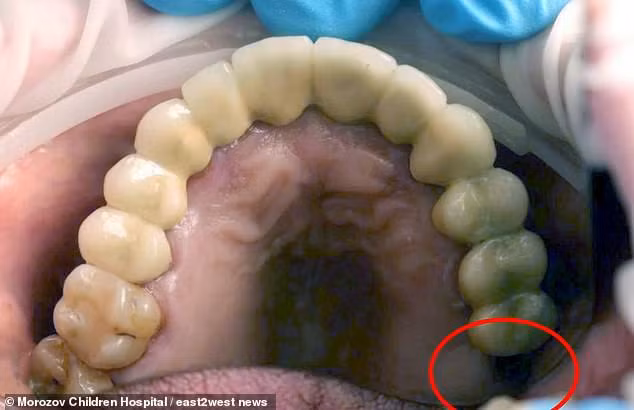

Hình ảnh trước và sau phẫu thuật cho thấy, hàm răng của bệnh nhân bị thiếu một chiếc răng hàm, nhưng thay vào đó, một chiếc răng đã phát triển ở một bên tinh hoàn của cậu bé.

Phần bị khuyết răng trong miệng của cậu bé 13 tuổi

“Chiếc răng là răng hàm thứ hai hoặc thứ bảy ở hàm trên. Nó thường được thay thế bằng răng vĩnh viễn khi lên 10-12 tuổi. Hình ảnh chụp cho thấy một cái gì đó bên trong tinh hoàn trông giống như sỏi thận”, bác sĩ phẫu thuật chia sẻ.